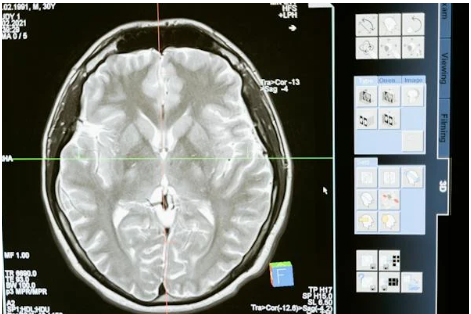

어린이 뇌의 구조와 기능: 발달의 핵심

뉴런은 뇌의 기본적인 세포 단위이며, 시냅스는 이 뉴런들 간의 연결 부위를 나타냅니다. 출생 후, 뇌는 뉴런을 무수히 만들어내고, 아기가 주변 환경과 상호 작용하면서 뇌는 사용되지 않는 뉴런들을 줄이고 중요한 연결을 강화하게 됩니다. 이 과정을 통해 어린이는 환경에 대한 적응력과 학습 능력을 키우게 됩니다. 어린이의 뇌는 특히 플라스티시티가 높습니다. 플라스티시티란 뇌가 새로운 정보에 적응하고 학습하는 능력을 의미합니다. 어린이가 다양한 경험을 할수록 뇌는 그에 맞게 구조를 발전시킵니다. 음악, 미술 등 다양한 분야의 활동이 어린이의 뇌 발달에 긍정적인 영향을 미치는 이유입니다. 어린이의 대뇌 피질은 추상적 사고, 문제 해결, 언어, 기억 등 고차원의 뇌 기능을 담당하는데 이 영역은 출생 후부터 지속적으로 발달하며 특히 언어 영역에서는 언어 습득과 함께 구조와 기능이 성숙해집니다. 어린이의 언어 발달은 뇌의 특정 부위의 발달과 깊은 관련이 있습니다. 초기 언어 학습은 뇌의 왼쪽 반구에서 주로 이루어지며 이 과정에서 어린이는 언어 소리를 듣고 의미를 이해하는 능력을 강화합니다. 글쓰기는 시각적 및 운동 피질과 관련이 깊어서 어린이의 손놀림과 글쓰기 능력은 뇌의 발달과 연결되어 있습니다. 어린이의 뇌 발달은 유아기와 소아기에 큰 변화를 겪습니다. 유아기에는 주로 운동 능력과 감각을 다듬고 소아기에는 추상적인 사고와 추상적인 개념을 이해하는 능력이 발전합니다. 이 기간에는 사회적 기술과 감정 조절도 뇌의 발달과 함께 진행됩니다.